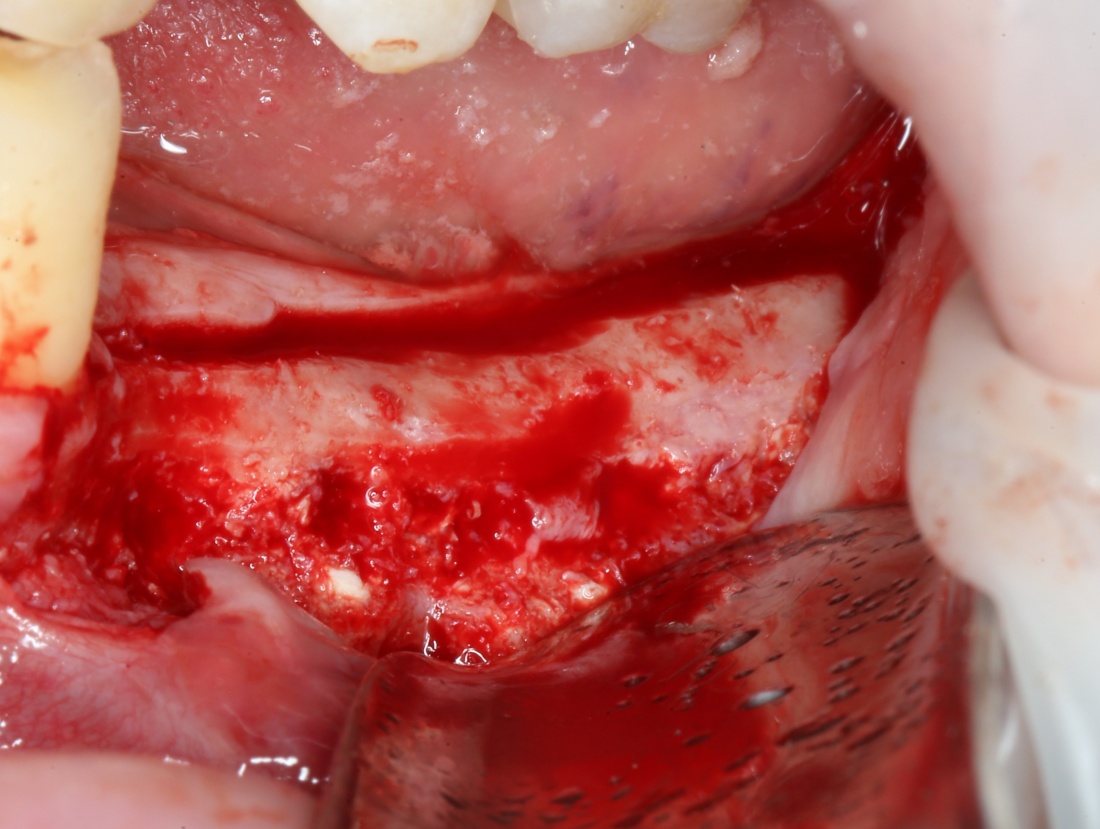

При горизонтальной остеотомии (вертикальной аугментации) очень удобен вестибулярный разрез по переходной складке или чуть ниже:

При вертикальной остеотомии (горизонтальной аугментации), наоборот, разрез делается по вершине альвеолярного гребня. При этом, «послабляющие» дополнительные разрезы не нужны.

3. Скелетирование альвеолярного гребня.